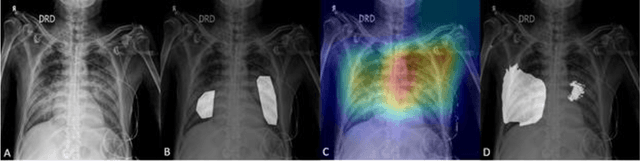

Abstract:COVID-19 is an infectious disease that causes respiratory problems similar to those caused by SARS-CoV (2003). Currently, swab samples are being used for its diagnosis. The most common testing method used is the RT-PCR method, which has high specificity but variable sensitivity. AI-based detection has the capability to overcome this drawback. In this paper, we propose a prospective method wherein we use chest CT scans to diagnose the patients for COVID-19 pneumonia. We use a set of open-source images, available as individual CT slices, and full CT scans from a private Indian Hospital to train our model. We build a 2D segmentation model using the U-Net architecture, which gives the output by marking out the region of infection. Our model achieves a sensitivity of 96.428% (95% CI: 88%-100%) and a specificity of 88.39% (95% CI: 82%-94%). Additionally, we derive a logic for converting our slice-level predictions to scan-level, which helps us reduce the false positives.